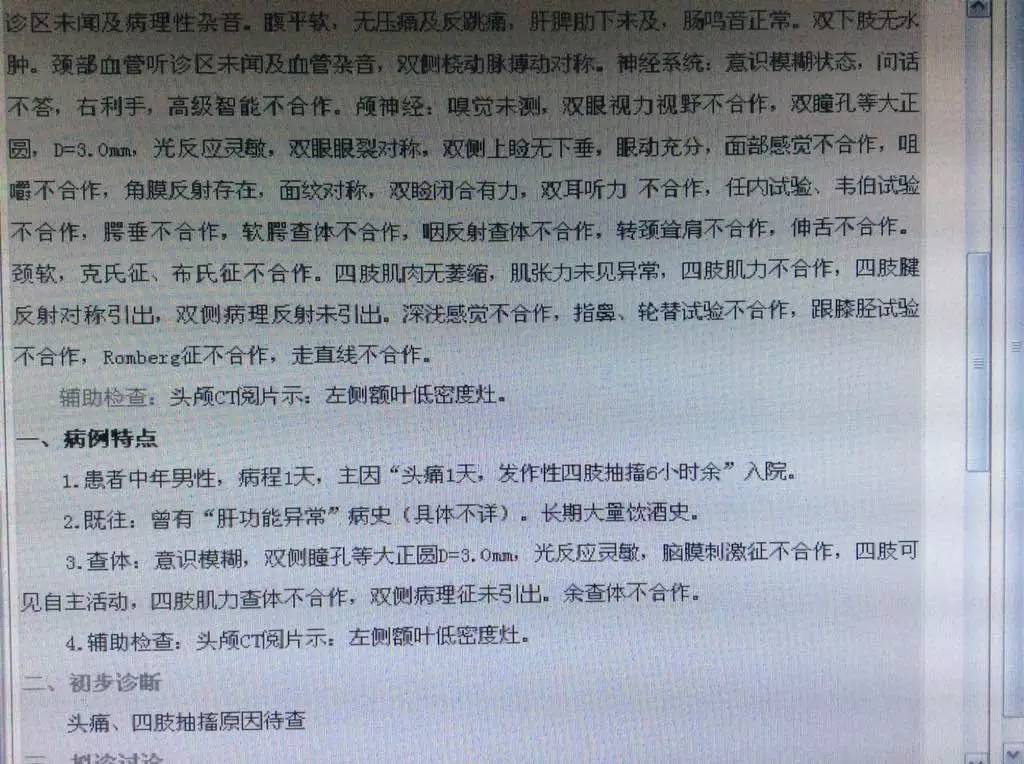

查体:生命体征平稳,意识模糊,双瞳孔正大等圆,光反射灵敏,余脑神经查体欠合作。四肢肌力、肌张力检查欠合作,双侧腱反射存在对称,感觉运动查体欠合作,双侧病理征(+)。颈抵抗。

辅助检查:

2016-3-24血常规示,白细胞计数10.35×109/L,淋巴细胞百分比1.4%,中性粒细胞百分比93.2%,中性粒细胞绝对值9.65×109/L。

2016-3-25生化全项示,AST47.5U/L,GGT128U/L。血沉80mm/h,CRP453mg/L。

2016-3-26甲功三项(-),术前四项(-),梅毒螺旋体抗体(+)。

2016-3-25腰穿压力>300mmH2O,细胞计数80×106/L,脑脊液蛋白5.432g/L,葡萄糖0.03mmol/L,氯化物112.3mmol/L,脑脊液IgG601mg/L。脑脊液墨汁染色(-),抗酸染色(-),间皮细胞30%,单核细胞30%,多核细胞40%。

咨询目的:

目前考虑中枢神经系统感染,进一步明确病因,帮助分析一下哪种可能性大?下一步检查及治疗?